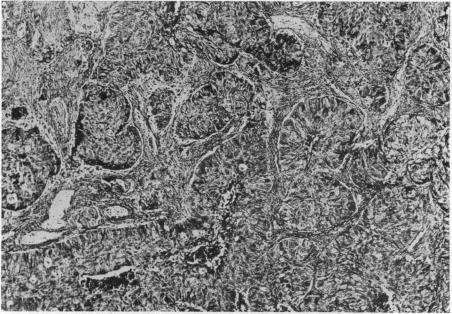

CONCERNING INTRACRANIAL MALIGNANT METASTASES: THEIR FREQUENCY AND THE VALUE OF SURGERY IN THEIR TREATMENT.

Ann Surg. 1926 Nov;84(5):635-46.